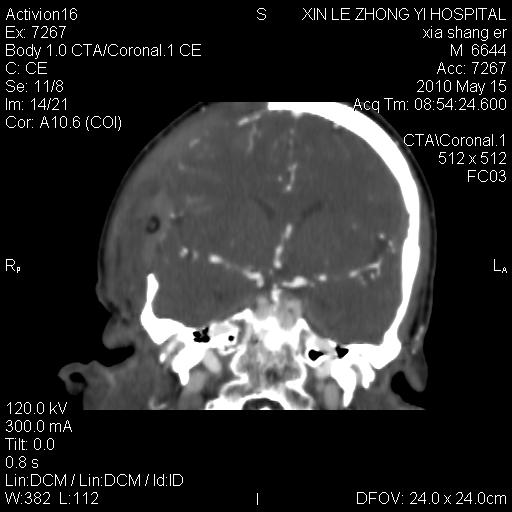

男.60岁,渐进性意识不清,ct检查双侧额颞顶部硬膜下血肿,开颅术后行脑血管cta,大脑中动脉起始部见一瘤状血管扩张。请各位老师留下宝贵意见

太常见了,报动脉瘤就可以

符合动脉瘤表现。

符合动脉瘤表现。

动脉瘤。

颅内动脉瘤。

后重建做得不是很好看,要将维蒂斯环充分显示,最好在增加一个mip。这样不好定位。

小动脉瘤

典型

符合动脉瘤的表现

动脉瘤

符合动脉瘤表现。

小动脉瘤

典型